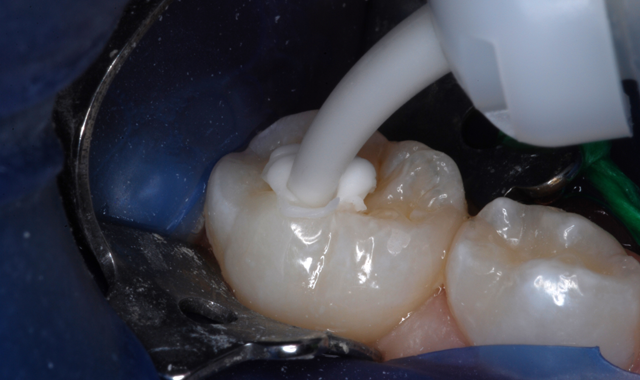

Recently, a mother brought in her 6-year-old daughter who had an occlusal caries lesion of a mandibular primary second molar (Fig. 1). I told the mother about all the advantages of glass ionomer filling materials, and I also related that KetacTM Universal, introduced in September of 2016, was the latest advancement and an excellent choice for her daughter’s treatment.

Fig. 1 Fig. 2

After appropriate local anesthesia, the tooth was isolated with a rubber dam, using the “slit dam” method (Fig. 2). Outline form was prepared using a high-speed diamond bur, exposing the extent of the caries lesion (Fig. 3). Carious dentin was debrided with slow-speed round burs and the cavity preparation was completed (Figs. 4 and 5).